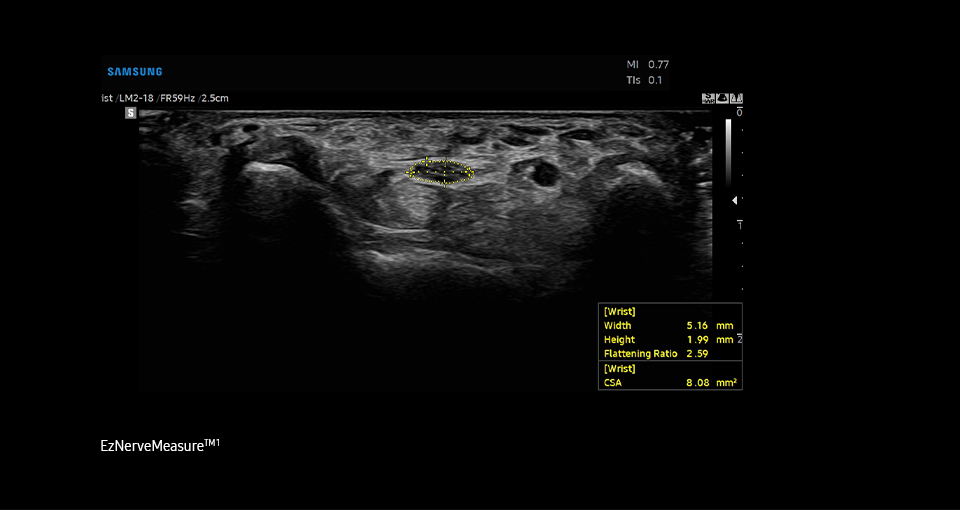

A semi-automated

measurement tool for nerve

EzNerveMeasure™ ¹ is a feature that provides measurement results

of the long axis, short axis, flattening ratio, and Cross-Sectional

Area of the detected nerve area.